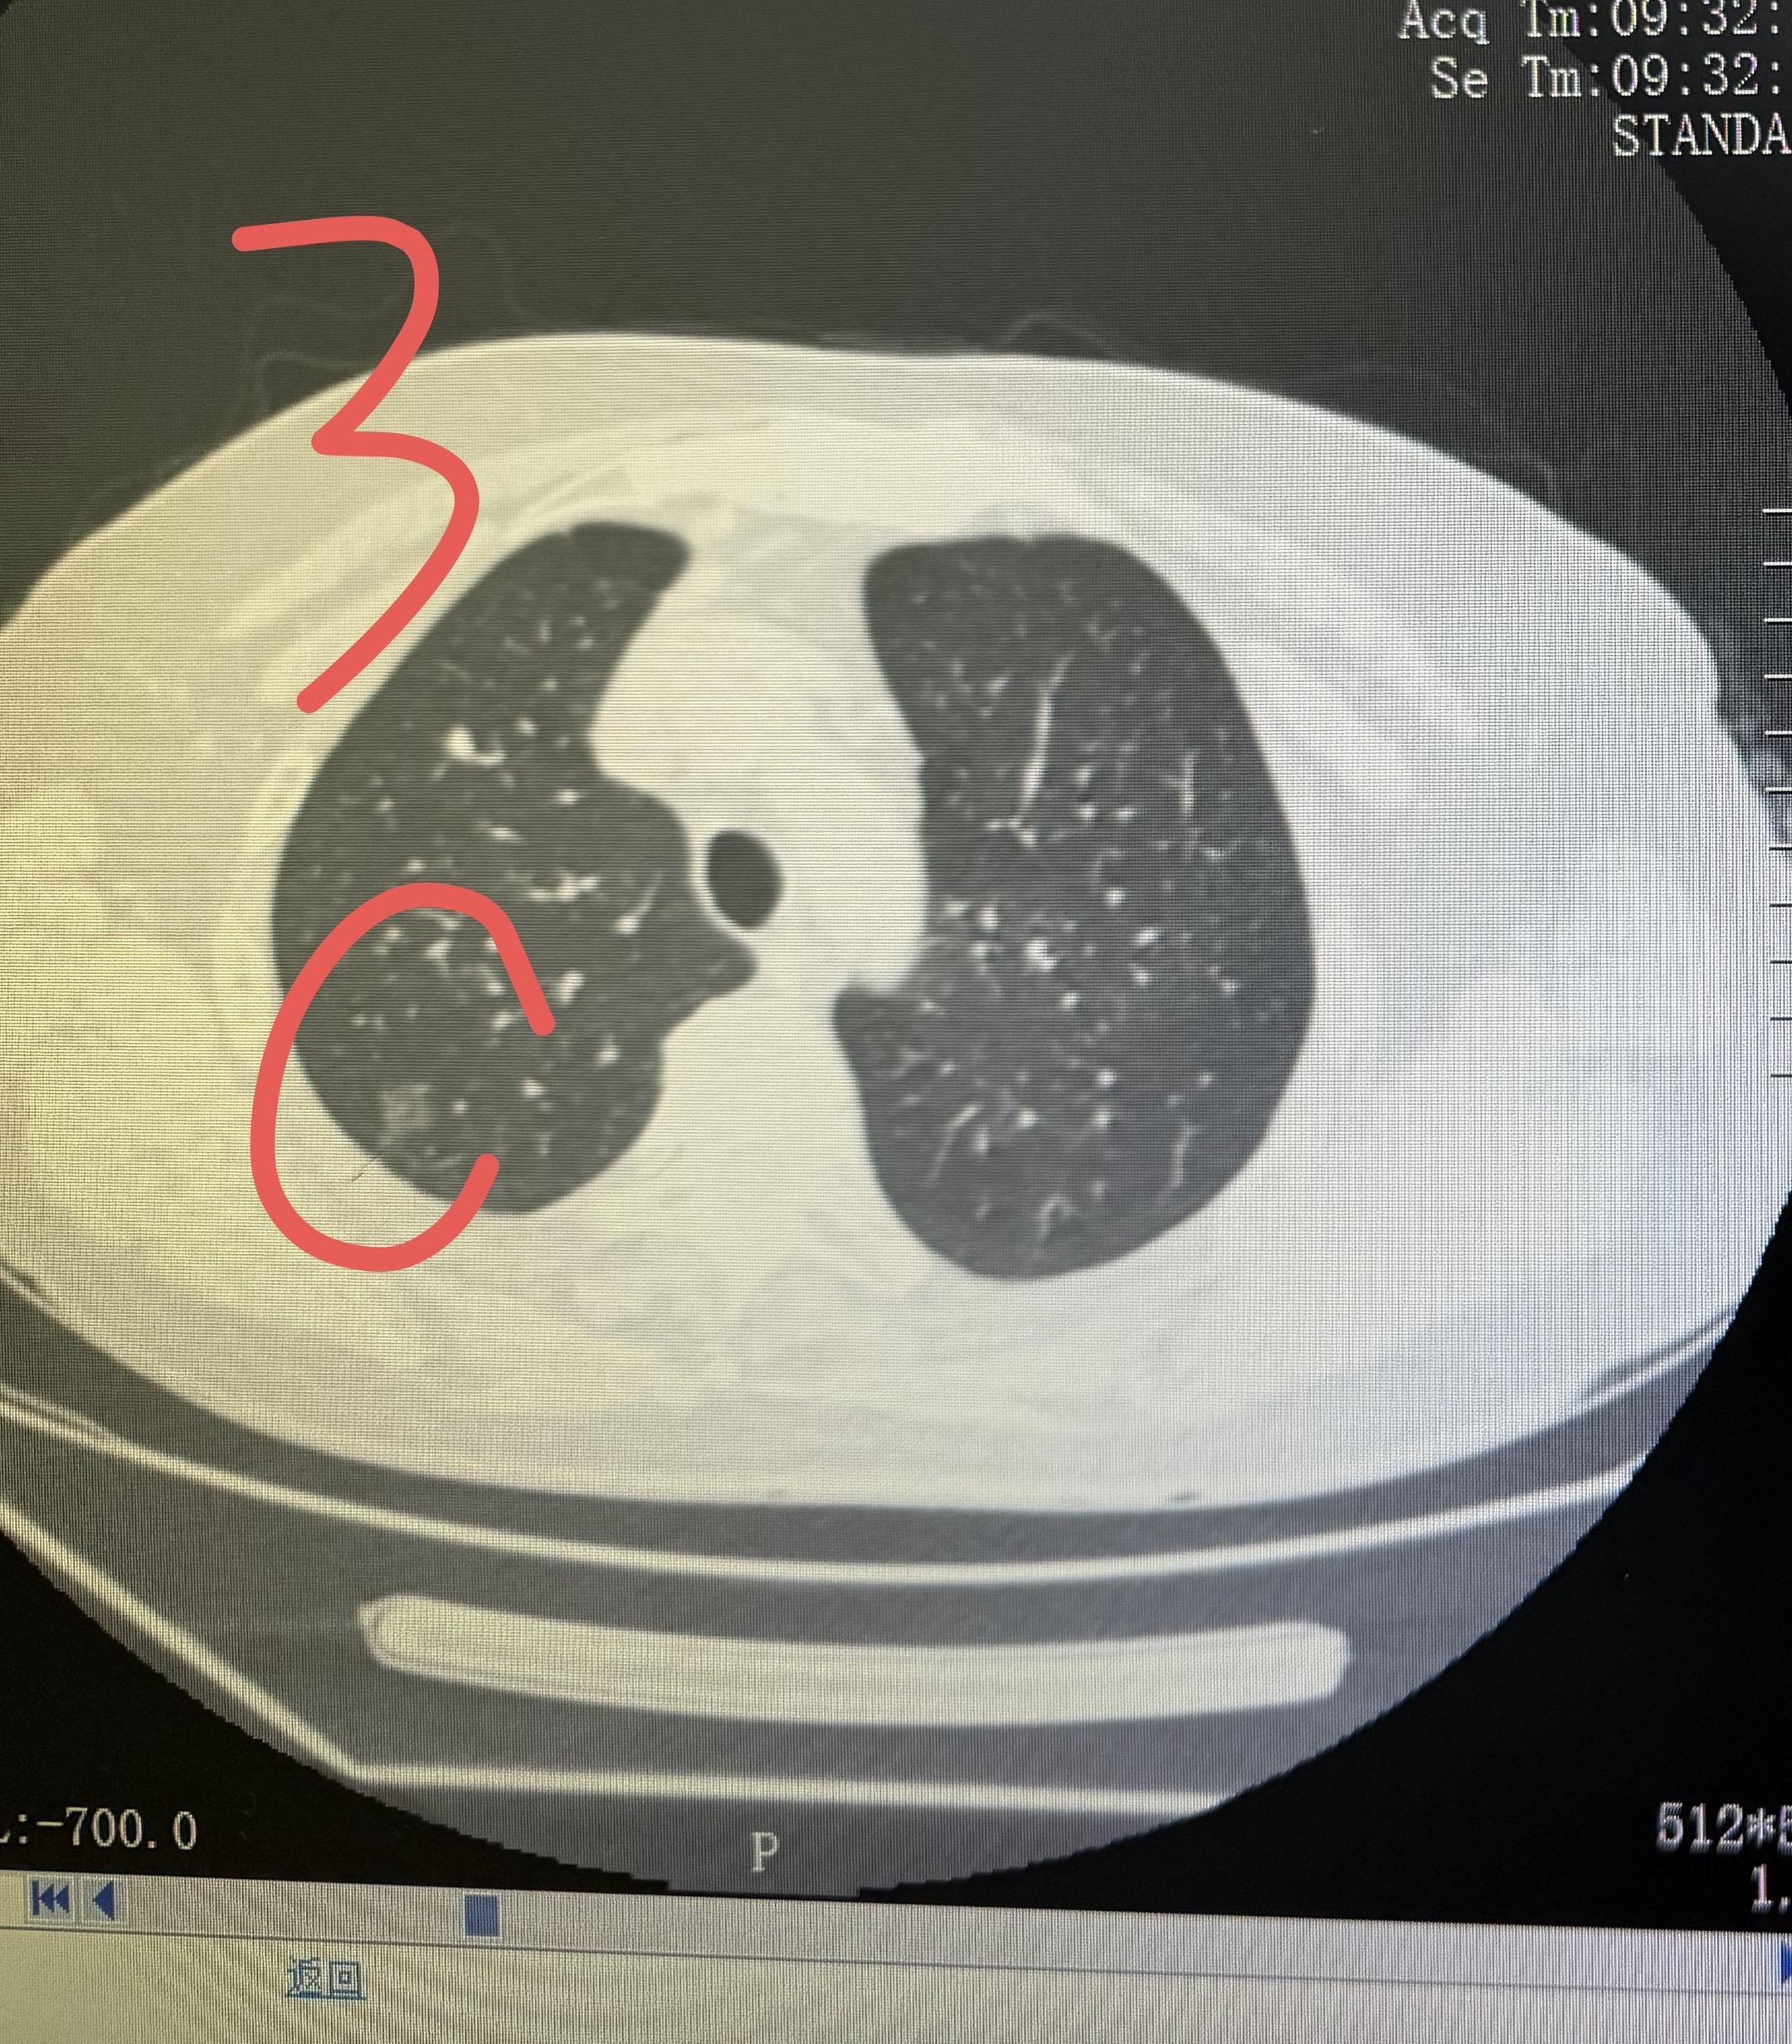

分享一个80岁多发结节的案例!如何治疗结。这个婆婆有4个有癌性磨玻璃结节,左侧两个1和2,右侧两个3和4。我们左侧做了腔镜楔形切除,术后病理浸润性腺癌,术后辅以治疗。右侧这两个结节在术后保守观察的过程中,明显缩小消失,应该是我们的术后辅助治疗起了作用。这就是,用一套治疗方案,解决了4个磨玻璃结节,该切的切,该保守的保守,病人损失最小化!